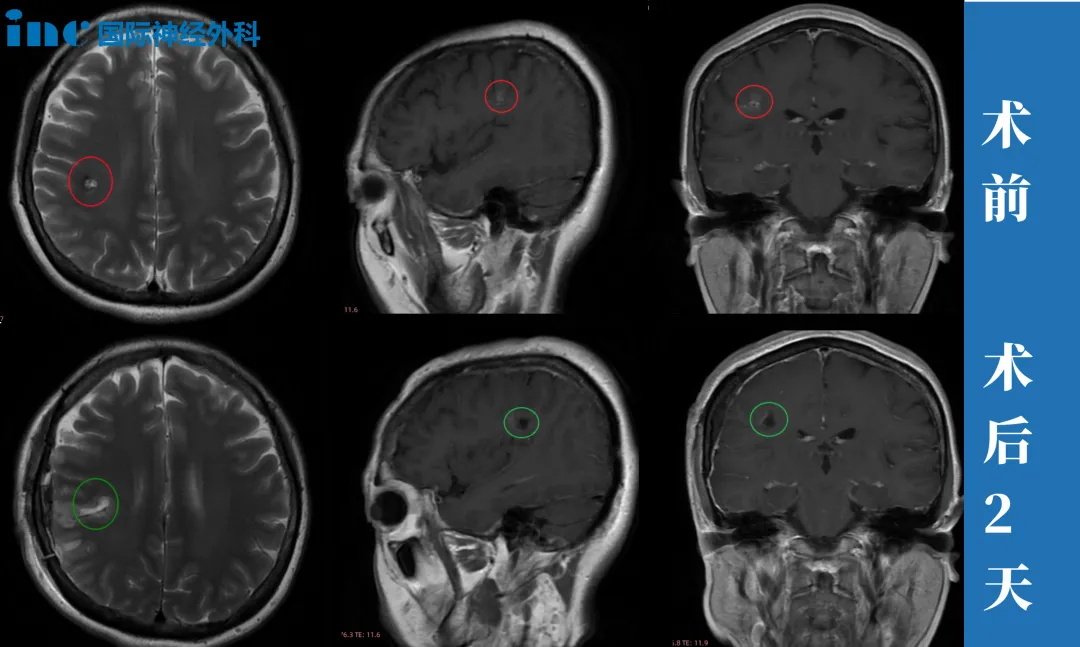

47岁女性,半卵圆中心海绵状血管瘤

简要病史:47岁的邓女士事业如日中天,对于工作,有着较强的责任心及较高的自我要求。一次定期体检却发现右脑额叶深部占位,大小约8mm,医生判断是海绵状血管瘤。咨询了上海的专家,但是医生的解释让他害怕,不建议手术,因为病灶部位太深,靠近功能区,手术风险大。而且目前病灶体积小,建议每年复查随访。查出海绵状血管瘤之后,邓女士发现有时工作太累了会头疼,近期还出现 6~7次无预兆性突然出现眼前漂浮物的现象,很快自行缓解。

治疗过程:2024年3月28日,巴教授中国行期间,一场疑难功能区海绵状血管瘤示范手术,成功拯救了47岁的邓女士于病魔的阴影之中。“I believe you, it’s a very (我很信任您,这是一个)就是正确的选择。”术后2小时,麻醉刚清醒,47岁的邓女士激动地用英语说出自己的术后感受,重新露出了大大的笑脸。

手术1天,顺利出ICU,转入普通病房,交流顺畅、肢体活动正常,恢复良好。“我的手有力量,Thank you very much!”此时的邓女士回归了往日的健谈、声音洪亮、神采奕奕。术后2天,邓女士表示已经可以自主下床活动,“已经可以走来走去”,巴教授查房用中文为邓女士点赞。